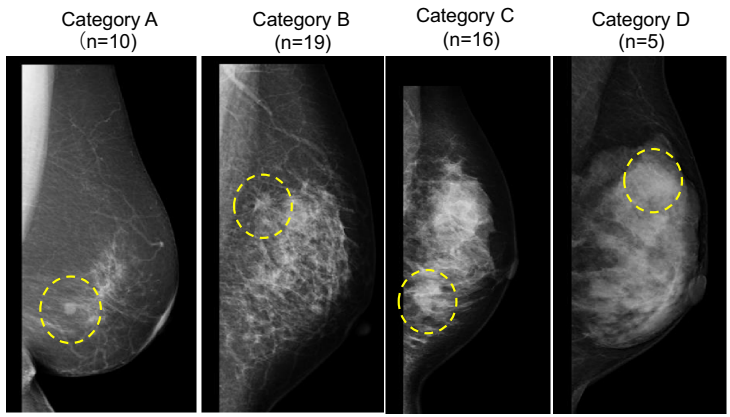

乳腺密度评估采用美国放射学会制定的乳腺影像报告和数据系统(Breast Imaging Reporting and Data System, BI-RADS)标准,由三名认证放射科医师独立读片,将乳腺密度分为四类:A类(几乎全部为脂肪)、B类(散在纤维腺体密度区)、C类(不均匀致密)和D类(极度致密)。对于分类不一致的情况,由资深放射科医师做出最终裁定。